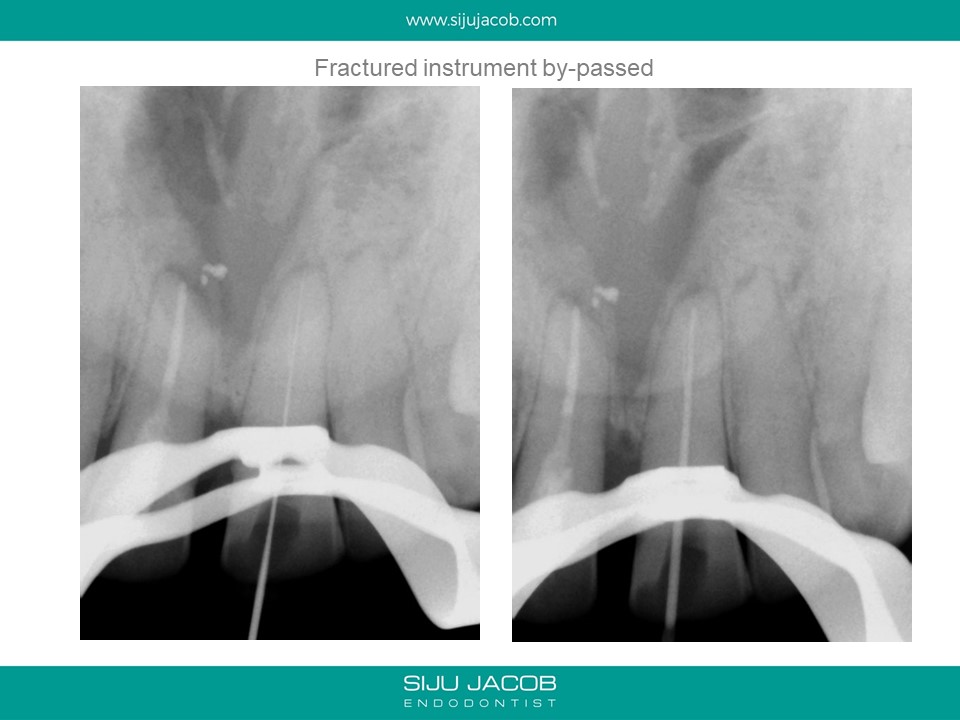

This was a case which was started by another clinican. A Naso-palatine cyst was mis-diagnosed as lesion of endodontic origin. The clinician opened up two central incisors, broke an instrument in one, couldn’t locate the canal (nearly perforated) and then referred the case.